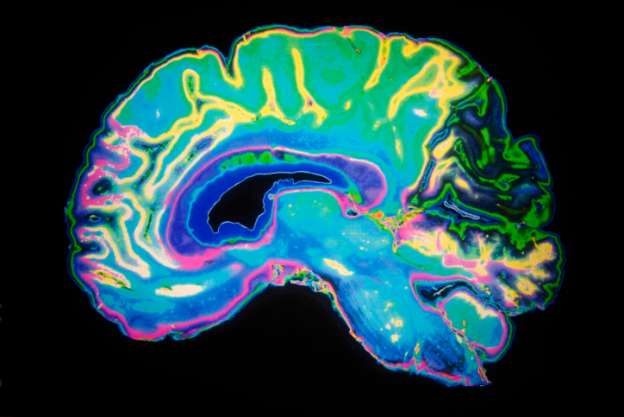

El equipo utilizó imágenes por resonancia magnética funcional (fMRI) para escanear los cerebros de 15 matemáticos profesionales y 15 no-matemáticos del mismo nivel académico. Mientras estaban en el escáner los sujetos escucharon una serie de 72 enunciados matemáticos de alto nivel, divididos en partes iguales entre álgebra, análisis, geometría y topología, así como 18 declaraciones de alto nivel no matemáticas (en su mayoría históricas). Tuvieron cuatro segundos para reflexionar sobre cada proposición y determinar si era verdadera, falsa o sin sentido.

Los investigadores hallaron que al escuchar las declaraciones relacionadas con matemáticas solamente los matemáticos activaban una red del cerebro que involucra las regiones intraparietal bilateral, prefrontal dorsal, y temporal inferior. Este circuito por lo general no se asocia con áreas involucradas en el procesamiento del lenguaje y la semántica, que se activaron en tanto matemáticos como no matemáticos al ser expuestos a los enunciados no matemáticos.